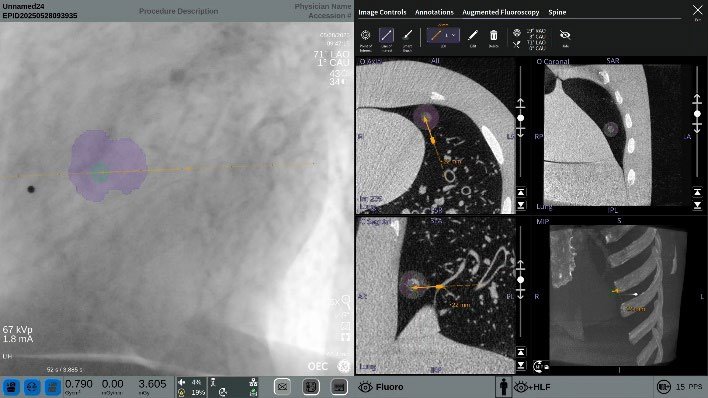

De OEC 3D Lung Suite combineert 3D cone beam CT-beeldvorming met realtime fluoroscopie om bronchoscopieprocedures nauwkeuriger en efficiënter te maken. Dankzij geavanceerde visualisatietools ondersteunt deze oplossing clinici bij het lokaliseren van laesies en het bevestigen van instrumentpositie tijdens de procedure.

De OEC 3D Lung Suite is een software-uitbreiding voor de OEC 3D mobiele C-boog die bronchoscopieprocedures vereenvoudigt. Door 3D-beeldvorming te combineren met live fluoroscopie biedt het systeem beter inzicht in de longanatomie en helpt het bij het nauwkeurig lokaliseren van doelgebieden.

Met augmented fluoroscopie worden regio’s en referentielijnen uit 3D-beelden rechtstreeks op live beelden geprojecteerd, wat een precieze positionering van instrumenten mogelijk maakt.

- Overlay van 3D-informatie op live fluoroscopie

- Target Points en Line of Interest

- Bullseye View (top-down)

- Progress View (perpendiculair)